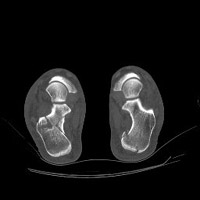

- Click on the image for a larger versionDAxial CT. This image better demonstrates the comminuted calcaneal fracture.